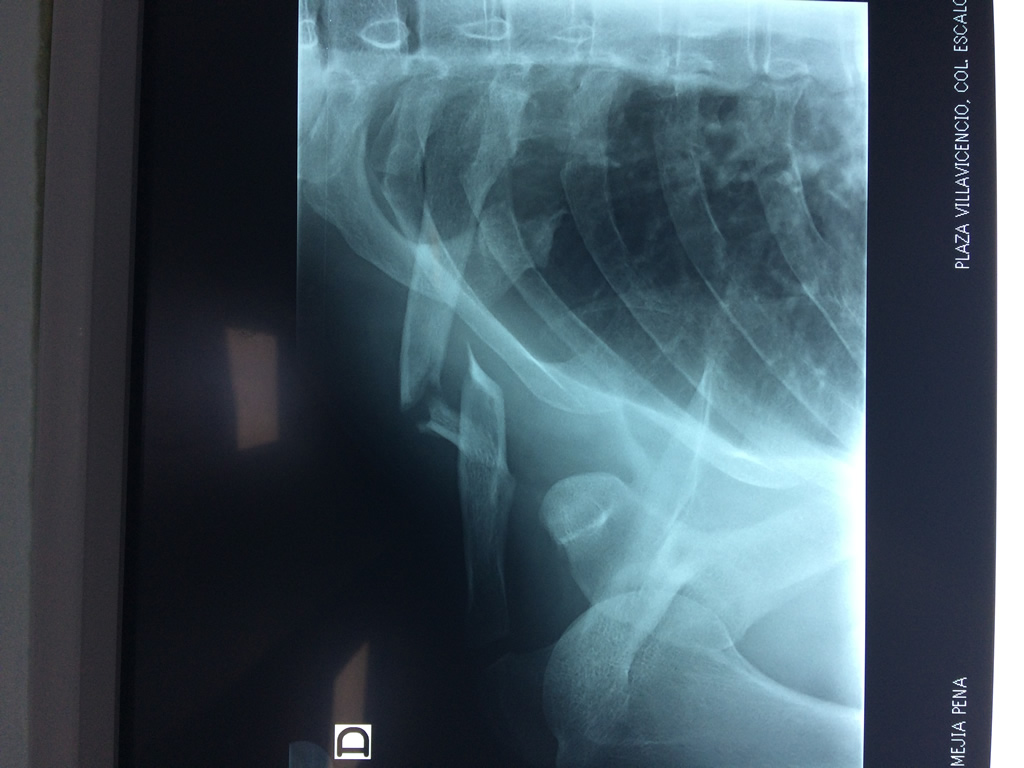

Cirugías de Codo - Clavícula

La clavícula es un hueso largo, con forma de "S" itálica, situado en la parte anterosuperior del tórax. Junto con la escápula forman la cintura escapular. Se puede palpar por toda su longitud y se extiende del esternón al acromion de la escápula, siguiendo una dirección oblicua lateral y posterior.

Se considera el único medio de unión entre el miembro superior y el tórax. A pesar de su aspecto, similar al de un hueso largo, posee una estructura semejante a la de un hueso plano, ya que carece de epífisis y de diáfisis, lo que la harían entrar dentro de la clasificación de hueso largo. Carece de un canal medular propiamente dicho.